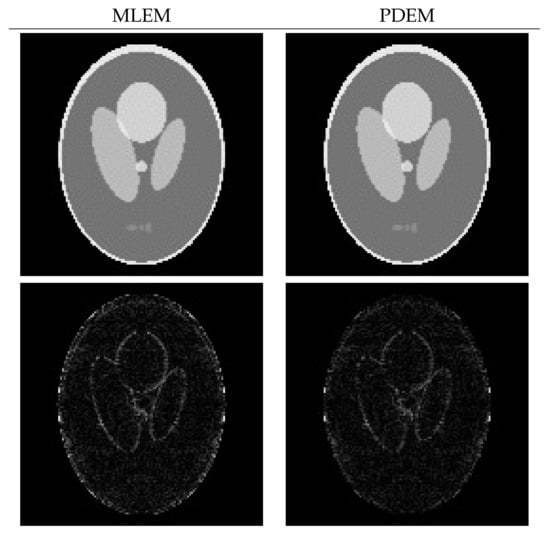

4.2. Reconstruction Using Physical Phantom